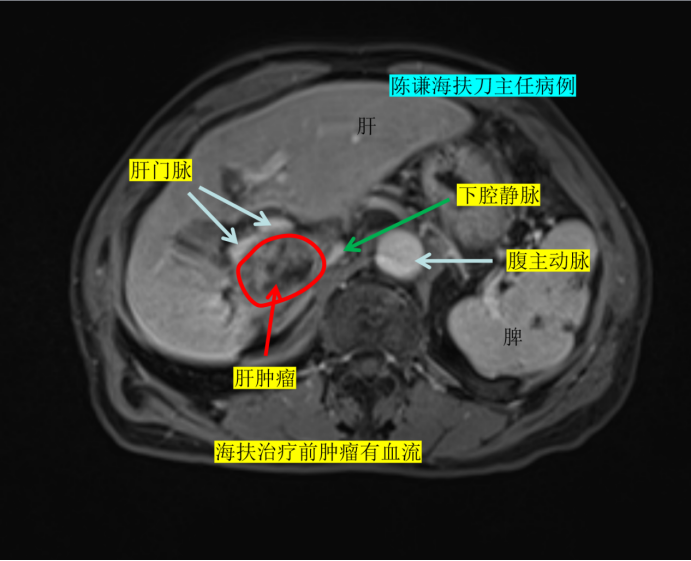

复查增强磁共振结果显示,老人的肿瘤位置极为刁钻——紧邻门静脉、下腔静脉,旁侧是胆囊,头侧靠近肝静脉。如此复杂的病灶环境,让常规消融治疗陷入困境:治疗风险极高,不仅极易损伤周边重要血管,还可能累及胆囊、肠道等邻近器官,治疗方案一度难以推进。

幸运的是,手术过程十分顺利,术中消融效果达到预期。术后复查增强磁共振显示,病灶实现消融满意,门静脉、下腔静脉、肝静脉等重要血管均未受损伤,老人术后第二天便顺利出院,恢复情况超出预期。